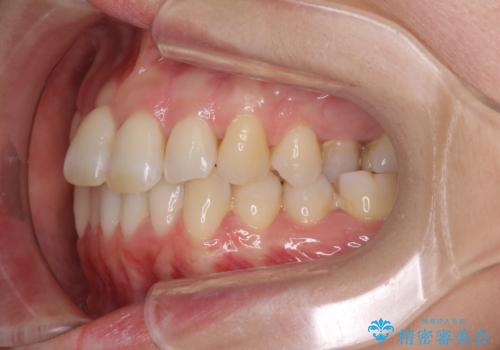

- 奥歯の咬み合わせを気にして来院された患者様です。

上顎骨の幅が下顎骨よりも小さいので、拡大装置により骨幅を広げて上下関係を改善し、その後インビザラインにて歯並びを整えることとしました。

上下の骨幅を改善したことで、スムーズに歯列矯正を行うことができました。

奥歯の咬み合わせを改善する必要があったため、治療は長期化しましたが、きっちりと仕上げることができました。